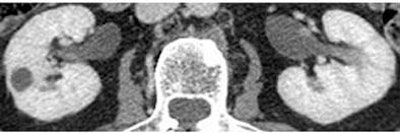

| Parenchymal phase (above), excretory phase (below), and MIP images (bottom) from a patient with a high-grade superficial recurrence of transitional cell carcinoma in the left renal pelvis. Images courtesy of Dr. Theresa Koppie. |

The researchers evaluated the CT images for hydronephrosis, filling defects, strictures, thickening, renal pelvis, ureters, anastomosis, and periureteral soft-tissue changes. They found 13 cases of hydronephrosis, nine patients with filling defects ranging from 5 mm to 1.5 cm, and seven patients with periureteral stranding. Periureteral stranding occurred most commonly in the distal left ureter in the region where it crossed the left mesentery, she said. Calculi were found in two patients. Eight of the 47 patients had cancer recurrence, all histologically proven transitional-cell carcinomas obtained during open surgery, Koppie said.

"All of the patients who developed some kind of a cancer in the upper tracts (renal pelvis, calyces, ureter) had a positive CT urogram," Koppie said. CT was 100% sensitive, and 30.8% specific, for upper-tract disease recurrence.